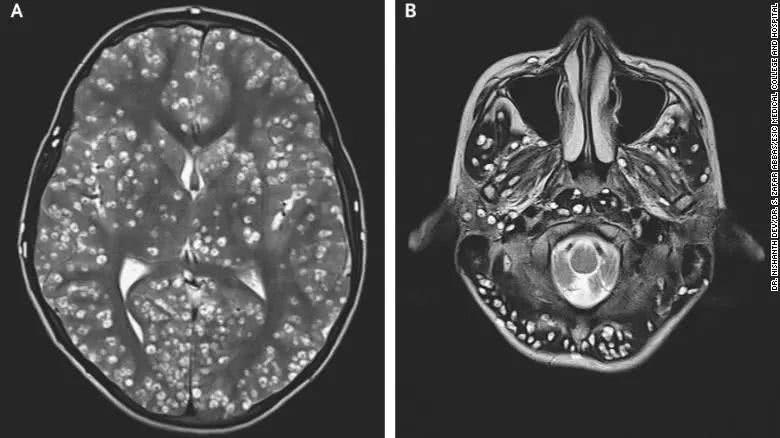

随州小伙脑内现寄生虫致身体萎缩 或因食用未熟蛙肉

吃进去的寄生虫,它可能爬呀爬,就爬到脑子里去了